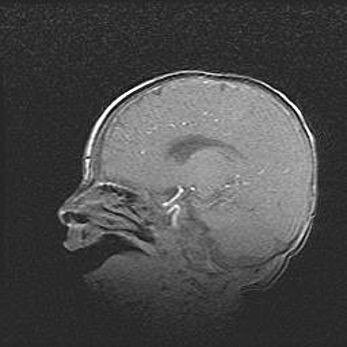

Наружная гидроцефалия с возможной атрофией височных областей.

Возраст: 28 дней

Вес: 3670 г

Пол: мужской

Окружность головы: 38 см

Срок гестации: 40 недель

Гидроцефалия головного мозга у новорожденных – это заболевание, которое характеризуется скоплением избыточного количества спинномозговой жидкости в желудочковой системе головного мозга в результате затруднения её перемещения от места выработки к месту поглощения в кровеносную систему или вследствие нарушения абсорбции. При открытой наружной форме гидроцефалии у новорожденных расширяются и переполняются субарахноидные пространства.

При нормотензивных  формах,  которые,  как  правило,  являются  следствием  перенесенных ишемических  повреждений  паренхимы  мозга,  возможно  сочетание микроцефалии  с нормотензивной гидроцефалией. В основе данных изменений лежит атрофия больших полушарий с преимущественной  локализацией  в  лобно-височных  областях.